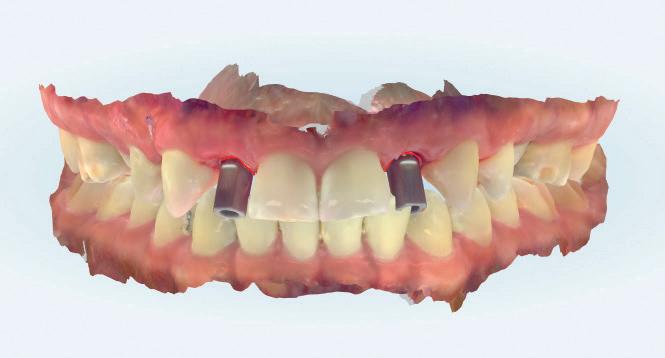

CASE STUDY

Guided implant approach for reproducible results, page 28

1. Adaptable to different guided surgery protocols: piloted, semi-guided or fully guided.

2. No friction between drills and guide sleeve, no overheating and no release of particles.

3. No specific drills and a very small surgical box.

4. Full control of drilling depth.

5. Your conventional driver-guided drilling sequence.